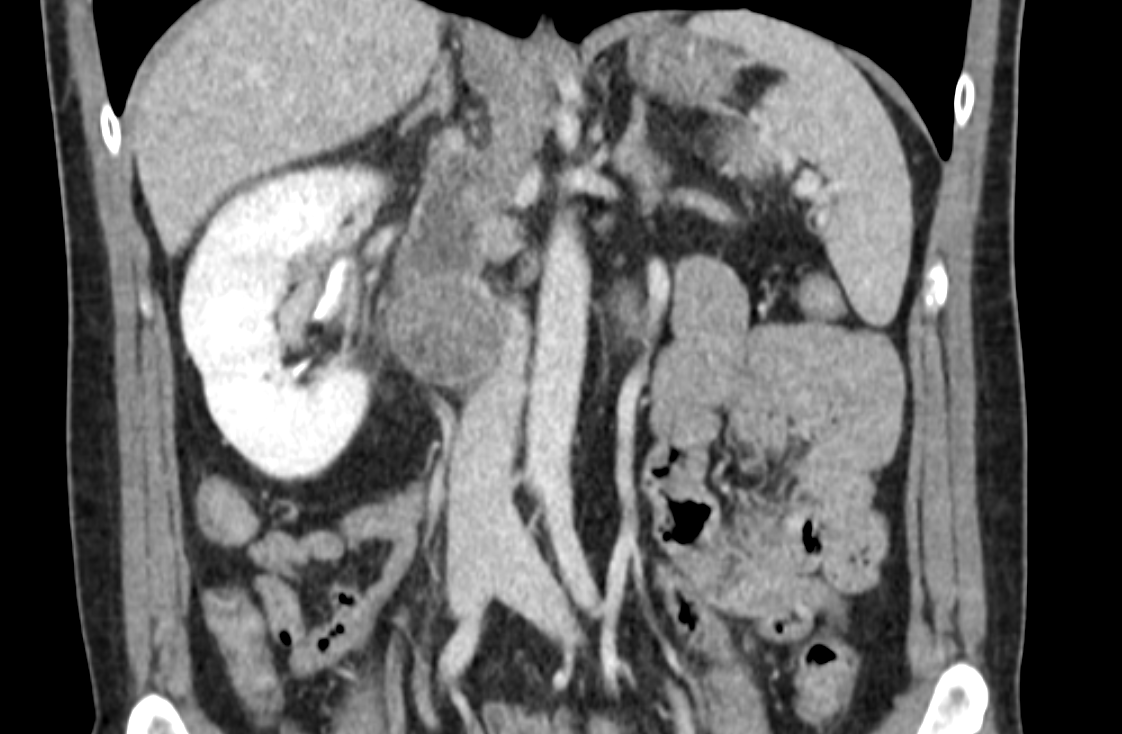

48 years old. 6 cm completely endophytic right kidney mass. Hilar cN1 4 cm. Atrophic left kidney. No symptom, no comorbidity. What to do? #robotics #open #partial #nephrectomy #LND #neoadjuvant #biopsy ???